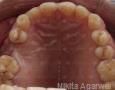

Pictures

6 Months

1 Year

IMPLANT PLACEMENT: